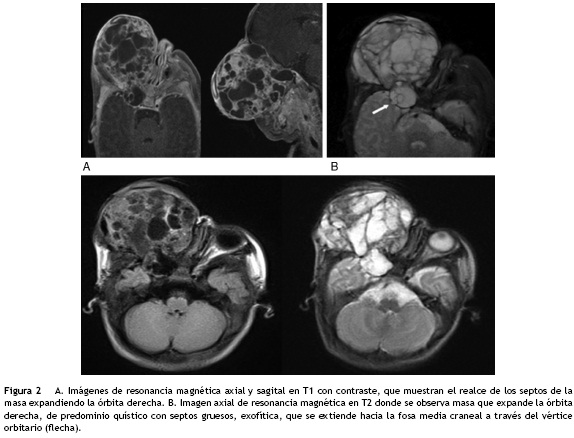

Se le practicó resonancia nuclear magnética cerebral y de órbitas en la que se observó una masa de señal heterogénea de 54 x 57 x 75 mm que reemplazaba el contenido orbitario derecho, con remodelación y destrucción parcial de las paredes orbitarias, crecimiento exofítico y múltiples áreas quísticas con invasión intracraneal por extensión a través del vértice orbitario hacia la fosa craneal media. Los componentes sólidos de la lesión realzaban de forma heterogénea con el contraste. La órbita izquierda no presentaba alteraciones (fig. 2).